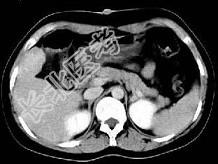

- 单项选择题根据所提供的图像,最可能的诊断为 ( )

A、肝平滑肌瘤

B、肝癌

C、肝血管瘤

D、局灶性结节增生

E、肝囊肿